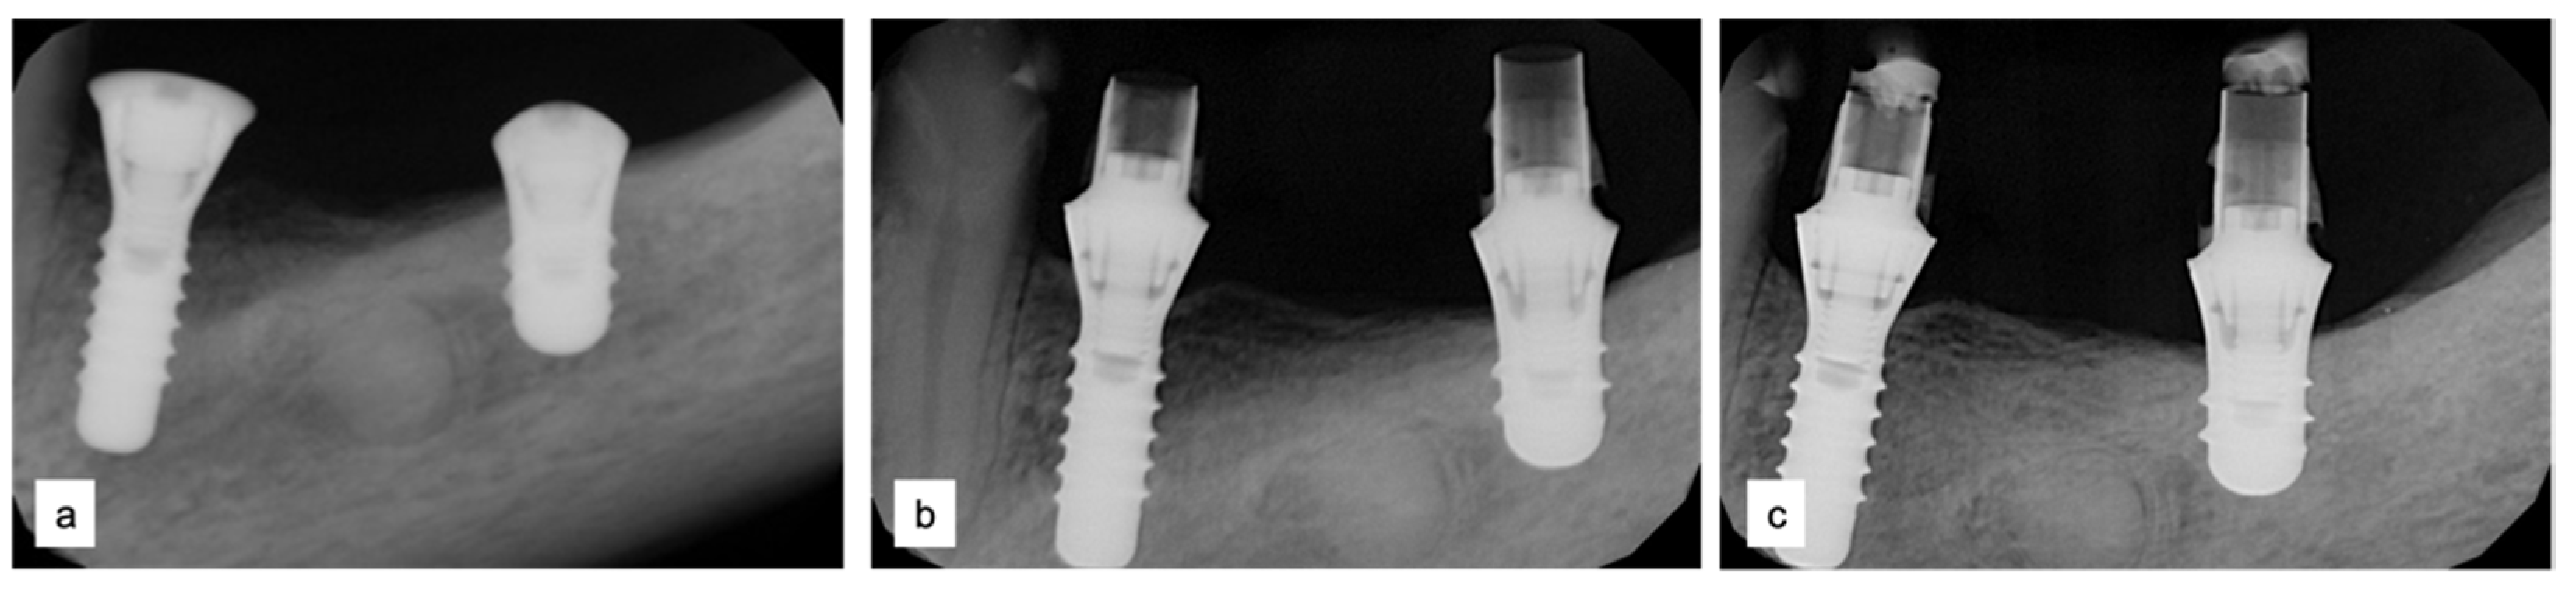

Figure 9.

Periapical radiographs (a) immediately after implant placement (Institute Straumann, Basel, Switzerland), (b) after 12 months, and (c) after 18 months of prosthetic loading.

Two implants (Institute Straumann, Basel, Switzerland) of 4 × 12 mm and 5 × 8 mm were inserted in the 3.4 and 3.6 areas, respectively (Figure 9a). The final prosthesis was manufactured with a digital workflow and delivered after three months. The patient was monitored with clinical and radiographic evaluations 12 and 18 months after prosthetic loading. The clinical examination and the digital scans at 12 months of follow-up proved the efficacy of the regenerative approach (Figure 10 and Figure 11). The comparison between 12 (Figure 9b) and 18 month (Figure 9c) radiographs showed stability of the bone crest around the dental implants. Furthermore, a progressive mineralization of the regenerated area was also evident (Figure 9a–c).